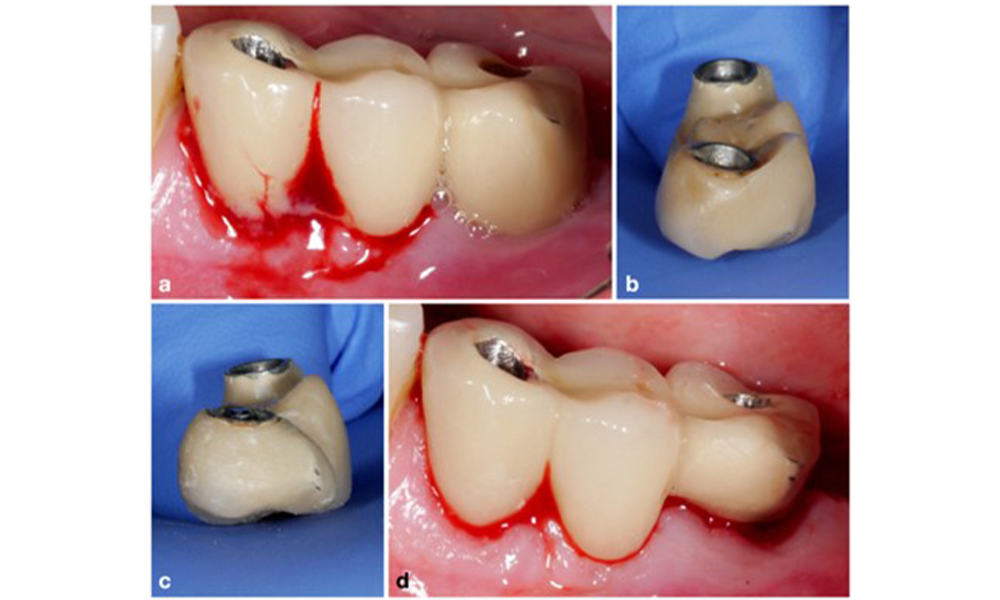

По време на Световния семинар за класификация на пародонталните и периимплантни заболявания и състояния през 2017 г. бяха определени диагностичните критерии за периимплантатен мукозит и периимплантит (Renvert et al. 2018). Периимплантният мукозит се дефинира като (1) наличие на възпаление около импланта (т.е. зачервяване, подуване, линия или капки кръв в рамките на 30 секунди от сондирането), но (2) без допълнителна костна загуба след първоначалното заздравяване (фигура 1 ).

Имплант в позиция 26 с периимплантатен мукозит (a–c). Дълбочината на сондиране от 5 mm (b) съответства на измерването, направено няколко седмици след поставянето на протезната реконструкция. Има кървене при сондиране (c), но рентгеновата снимка не показва допълнителна костна загуба извън очакваната при маргинално костно ремоделиране (d).

Фигура 1. Имплант в позиция 26 с периимплантатен мукозит (a–c). Дълбочината на сондиране от 5 mm (b) съответства на измерването, направено няколко седмици след поставянето на протезната реконструкция. Има кървене при сондиране (c), но рентгеновата снимка не показва допълнителна костна загуба извън очакваната при маргинално костно ремоделиране (d).